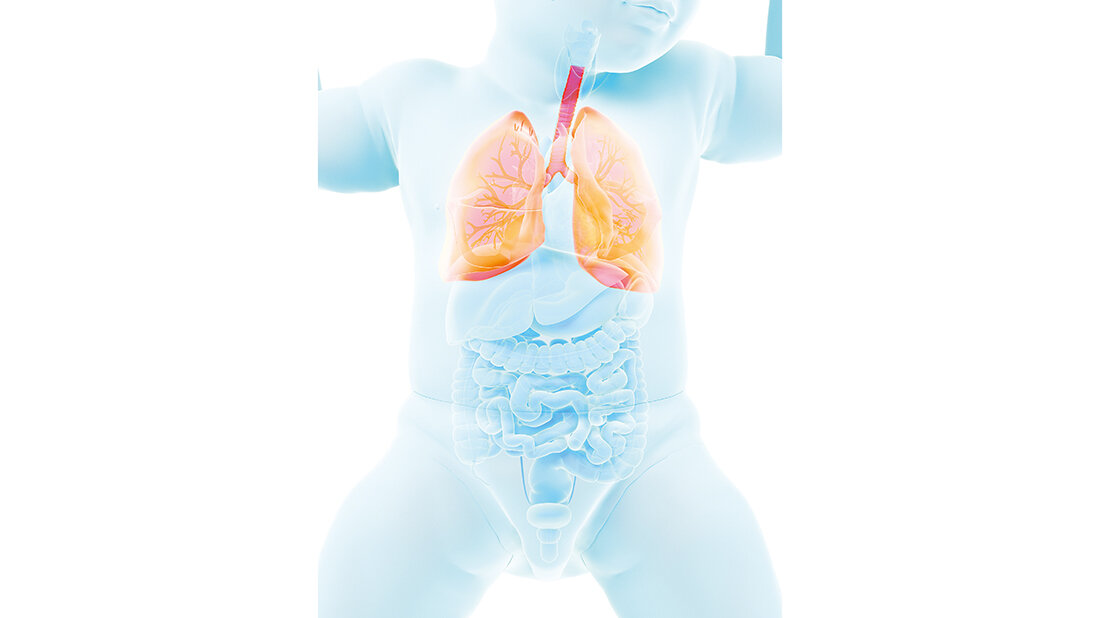

Die Röntgenaufnahme der Lunge ist eine der häufigsten Aufnahmen, auch im Kindesalter. Gerade für Röntgenabteilungen, in denen Kinder eher selten zu den Patienten zählen, ist sie eine Herausforderung.

X-ray imaging of the lungs is one of the most common types of imaging, even in children. It is a particular challenge for radiology departments, where children are rarely among the patients.